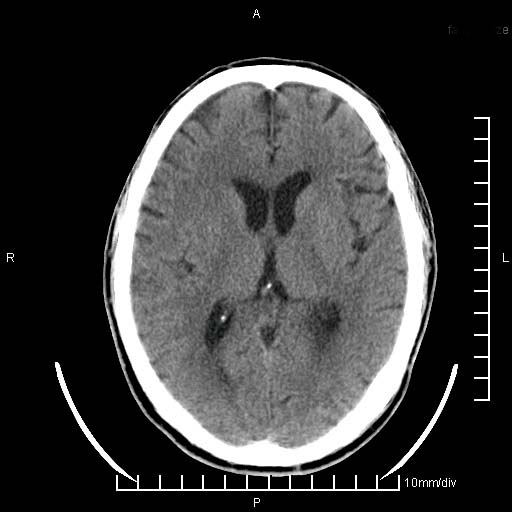

临床以双下肢浮肿,疼痛收治,无明显神经系统症状,既往无梗塞,出血病史。左颞叶见低密度灶,考虑什么?

考虑左侧颞叶脑软化灶。

无强化 无占位 软化灶吧

无强化、 无占位、局部脑沟增宽, 软化灶吧。